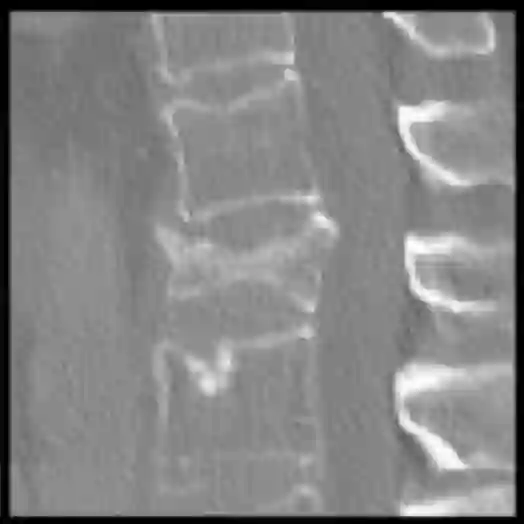

Vertebral fractures are a consequence of osteoporosis, with significant health implications for affected patients. Unfortunately, grading their severity using CT exams is hard and subjective, motivating automated grading methods. However, current approaches are hindered by imbalance and scarcity of data and a lack of interpretability. To address these challenges, this paper proposes a novel approach that leverages unlabelled data to train a generative Diffusion Autoencoder (DAE) model as an unsupervised feature extractor. We model fracture grading as a continuous regression, which is more reflective of the smooth progression of fractures. Specifically, we use a binary, supervised fracture classifier to construct a hyperplane in the DAE's latent space. We then regress the severity of the fracture as a function of the distance to this hyperplane, calibrating the results to the Genant scale. Importantly, the generative nature of our method allows us to visualize different grades of a given vertebra, providing interpretability and insight into the features that contribute to automated grading.